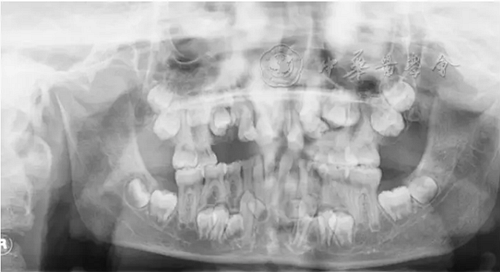

(1)疾病定義及口腔表現(xiàn):LCH是一組原因不明、以朗格漢斯細(xì)胞及其前體細(xì)胞克隆性增生為特點(diǎn)的疾病,又稱組織細(xì)胞增生癥X(histiocytosis X)。多見于20歲以下青少年。根據(jù)患者的發(fā)病年齡和臨床特點(diǎn)將其分為3型:嗜酸性肉芽腫、漢-許-克病和勒-雪病。口腔頜面部常見的為骨嗜酸細(xì)胞肉芽腫,好發(fā)于下頜磨牙區(qū)與下頜角部位,病變主要為溶骨性破壞。早期表現(xiàn)為慢性炎癥和局部無痛性膨隆,病變區(qū)牙槽黏膜糜爛、潰瘍;牙齦充血,形成深牙周袋。隨著病變進(jìn)展,出現(xiàn)牙齒松動(dòng)加重,病變區(qū)鈍痛,進(jìn)食時(shí)加劇,口臭明顯。拔除松動(dòng)牙后拔牙創(chuàng)經(jīng)久不愈,觸碰牙槽窩時(shí)疼痛劇烈。影像學(xué)檢查可見骨內(nèi)圓形或橢圓形低密度影(圖2),直徑數(shù)毫米至數(shù)厘米不等,邊緣較囊腫模糊。頜骨內(nèi)病損常延伸至牙槽嵴,形成牙齒懸浮的特征性影像。牙槽骨包括牙槽中隔呈水平或垂直向吸收,牙根吸收。

圖2 4歲朗格漢斯細(xì)胞組織細(xì)胞增生癥患兒的曲面體層X線片,可見右側(cè)下頜骨大面積橢圓形低密度影

(2)治療原則:根據(jù)病變范圍及受累部位不同,對LCH患者可采取手術(shù)治療、放射治療、化學(xué)治療、免疫治療及造血干細(xì)胞移植等治療方法,常需多學(xué)科綜合治療。病變區(qū)牙齒顯著松動(dòng)者可先不拔牙,待病情得到控制后再評(píng)估以明確治療方案。對有明顯牙周炎癥的患者,可進(jìn)行系統(tǒng)牙周治療,包括潔治,刮治和根面平整,維護(hù)口腔衛(wèi)生盡可能保留牙齒。